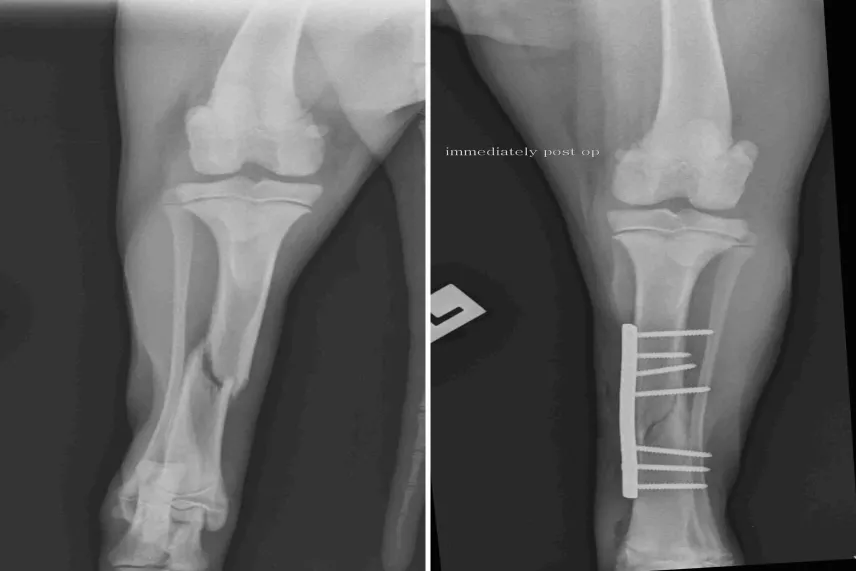

Фрактура на тибия при домашни любимци: Симптоми, лечение и възстановяване

Фрактурата на тибията (големия пищял) е едно от най-често срещаните наранявания при кучета и котк...